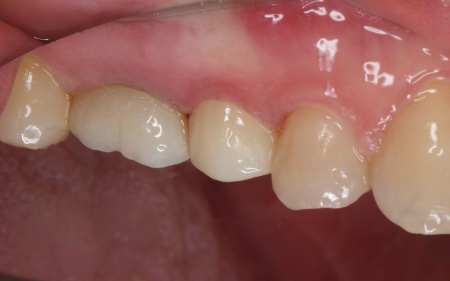

60代女性 割れた歯を抜かず審美性に優れたジルコニアの被せ物で修復した症例

被せ物については、自費診療の白い素材「セラミック」の中でも、強度と審美性に優れた「ジルコニア」を選択しています。

薬剤を歯根の先までしっかりと詰め、支台築造で土台を作製したあと、被せ物を作製しました。

最後に、完成した被せ物を装着し、噛み合わせや見た目に問題がないことを確認して、治療を終了しています。